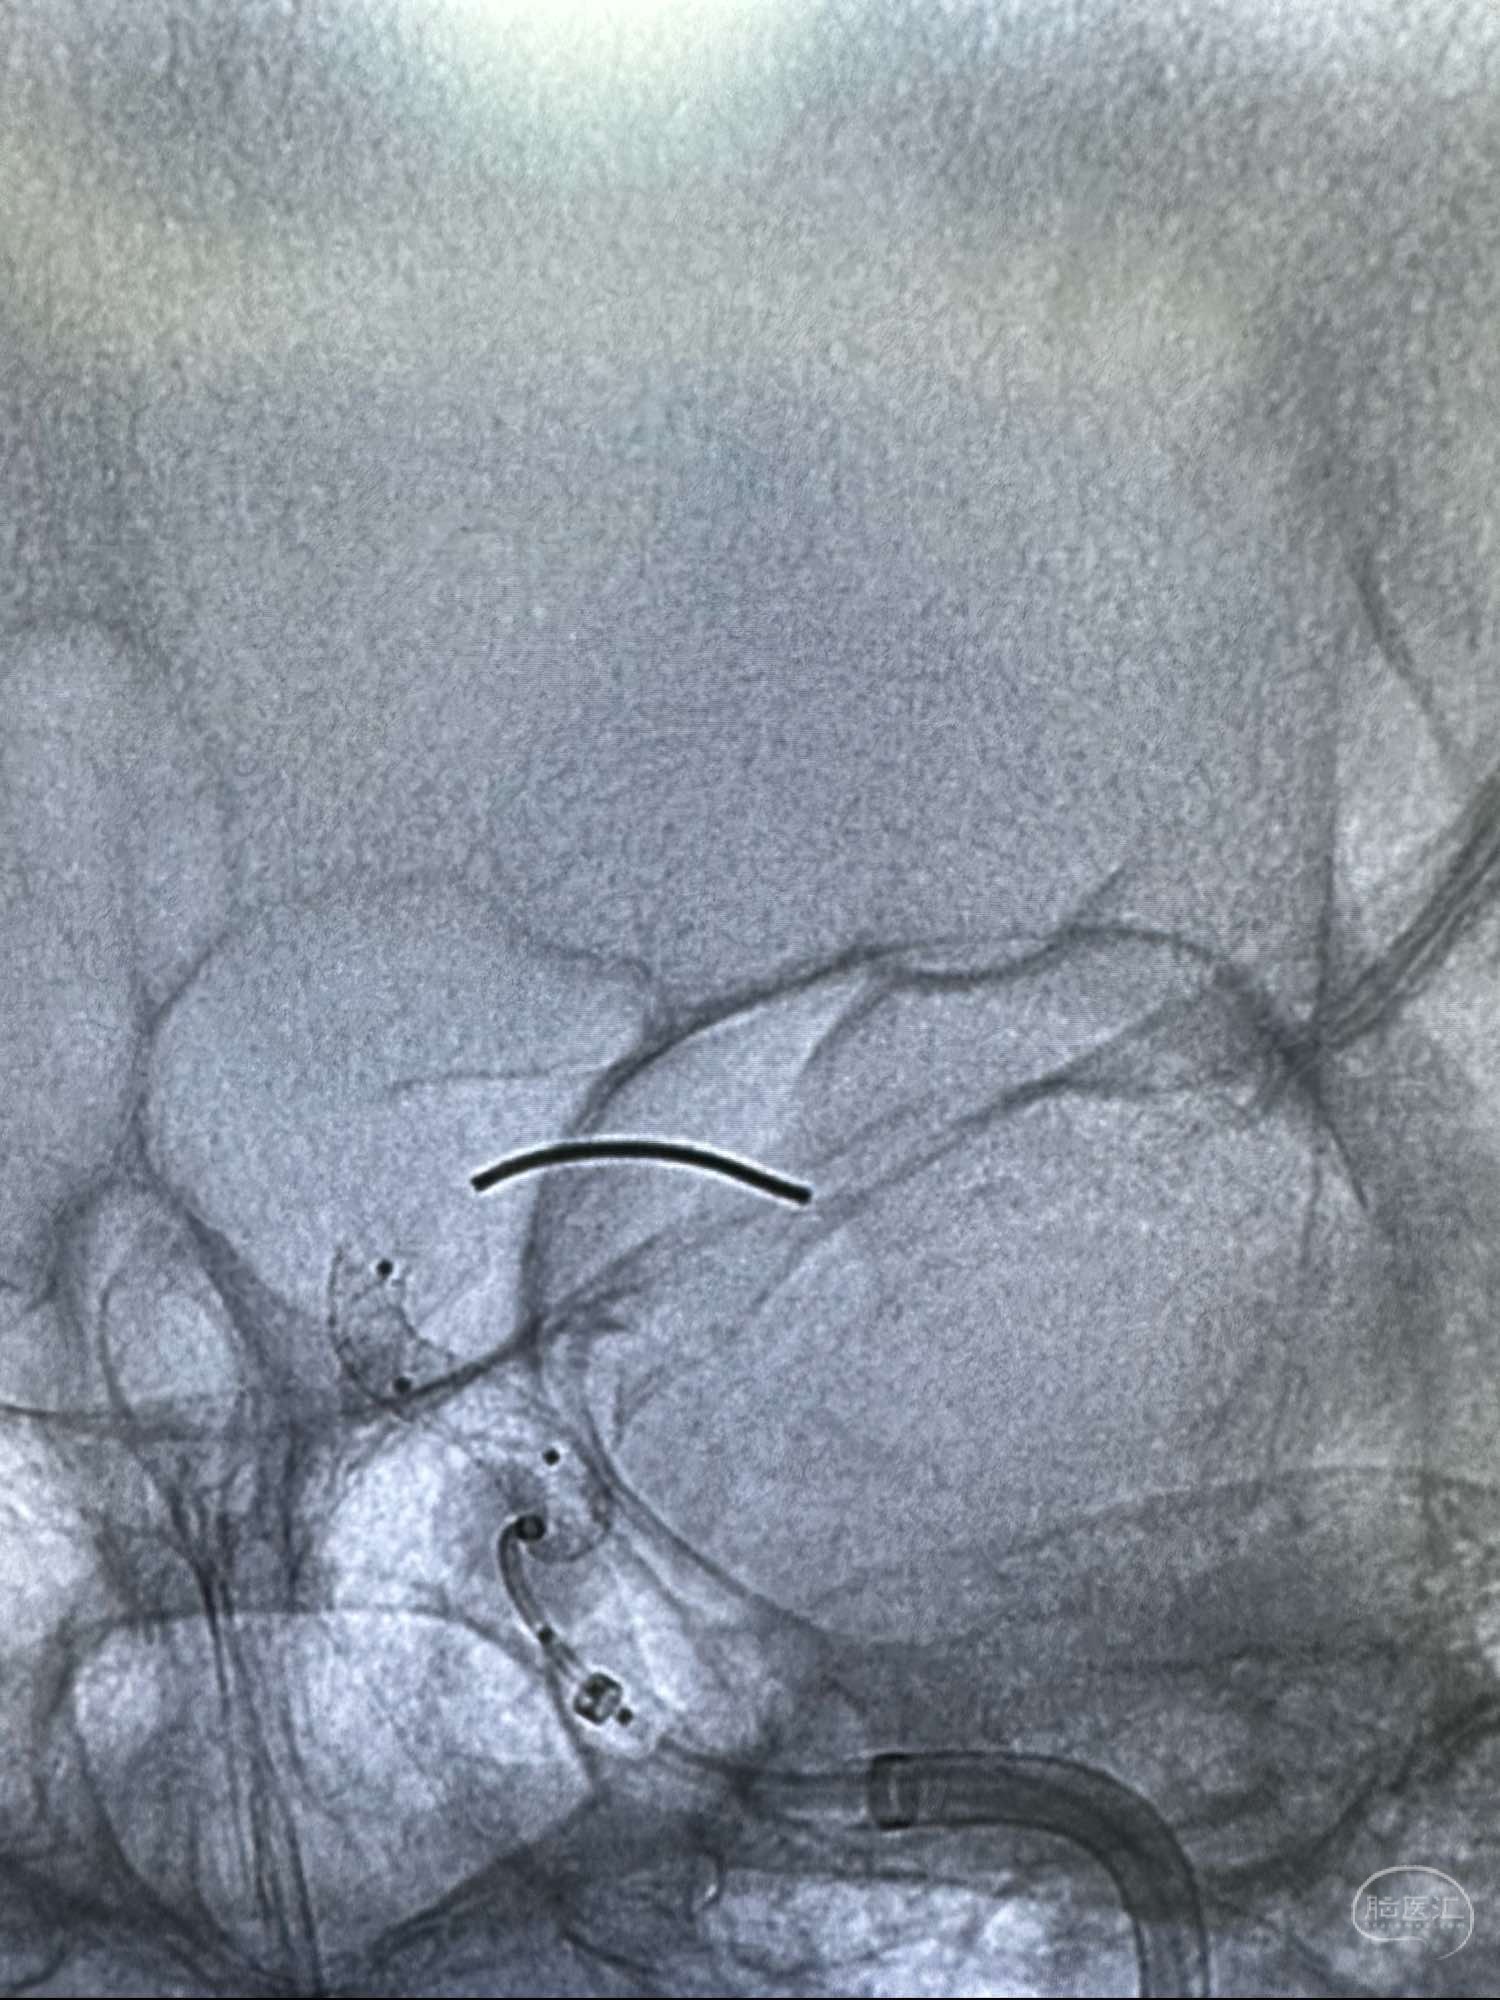

最后正位造影

侧位

侧位的动脉晚期

进行支架重建

另外一个角度见支架打开可